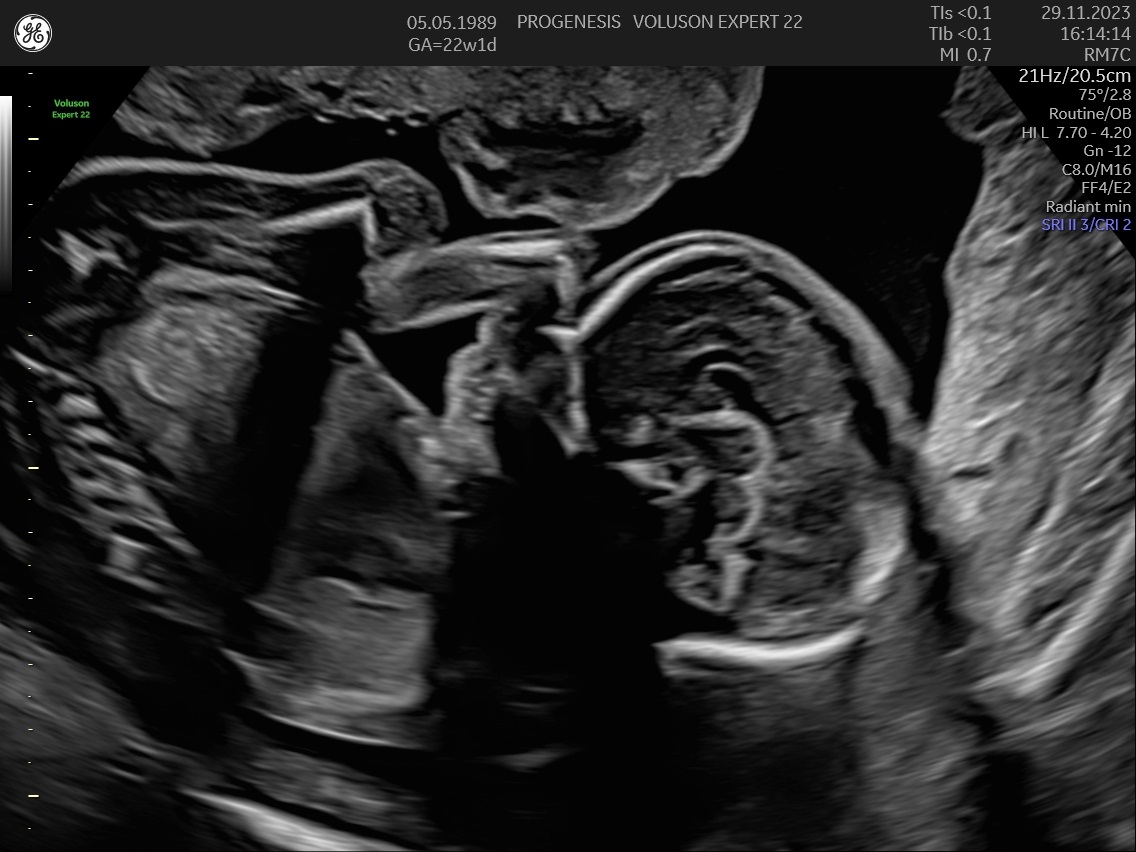

Υπερηχογράφημα Β΄Επιπέδου (20-24 εβδομάδων)

α) Η λεπτομερής αξιολόγηση της εμβρυϊκής ανατομίας, όπου αναγνωρίζονται τυχόν ανατομικές ανωμαλίες.

γ) Ο έλεγχος της ανάπτυξης του εμβρύου, του πλακούντα, του ομφαλίου λώρου και του αμνιακού υγρού.